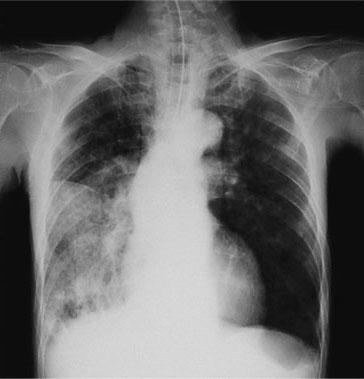

85歳の男性。脳梗塞の既往がある。2、3か月前から食事中にむせることが多くなっていた。3日前から元気がなく、昨晩から発熱と意識障害とがみられたため救急搬送され気管挿管の上、入院となった。体温38.0℃、呼吸数25/分、左胸部に肺胞呼吸音、右胸部に水泡音が聴取された。エックス線写真を示す。この患者の症状が生じている原因として最も考えられるのはどれか。

誤嚥性肺炎